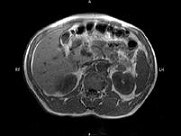

- 单项选择题男,52岁, 下肢无力伴多饮多尿2年余,实验室检查: 低血钾,血醛固酮水平及24h尿醛固酮定量超过正常值, MRI检查如图所示,应诊断为 ( )

A、左肾上腺囊肿

B、左肾上腺腺瘤

C、左肾上腺嗜铬细胞瘤

D、左肾上腺髓脂瘤

E、左肾上腺转移癌